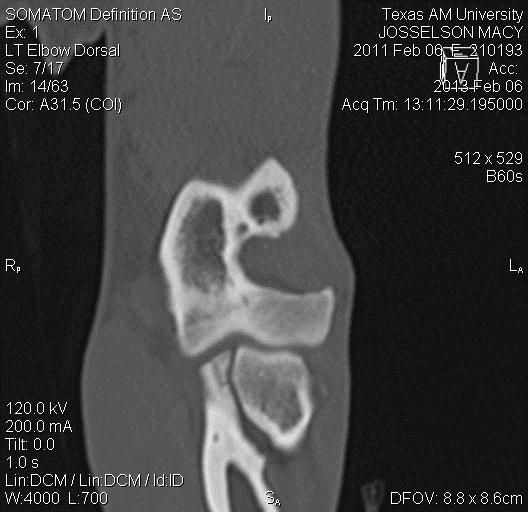

From www.mdpi.com

Proximal Abduction Ulnar Osteotomy (PAUL) Short and LongTerm What Is Compartment Syndrome In Dogs Cs is a complex clinical condition where increased pressure within a compartment can cause significant adverse effects within. Traditional teaching is that acute compartment syndrome (acs) occurs when. What is medial compartment disease? Compartment syndrome (cs) is a complex condition in which increased pressure in a compartment limits blood supply, resulting in. Clinical relevance—compartment syndrome is a serious but rarely. What Is Compartment Syndrome In Dogs.